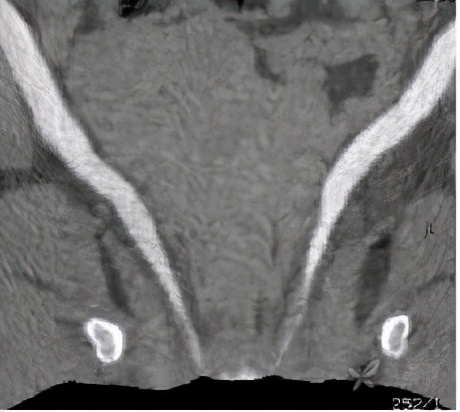

检查完成后,CT也印证了双肾积水的表现。

但是,双侧输尿管走行区未见明显梗阻的因素。

同时也发现了异常表现:双侧输尿管开口过低,似乎不是正常的膀胱三角区。